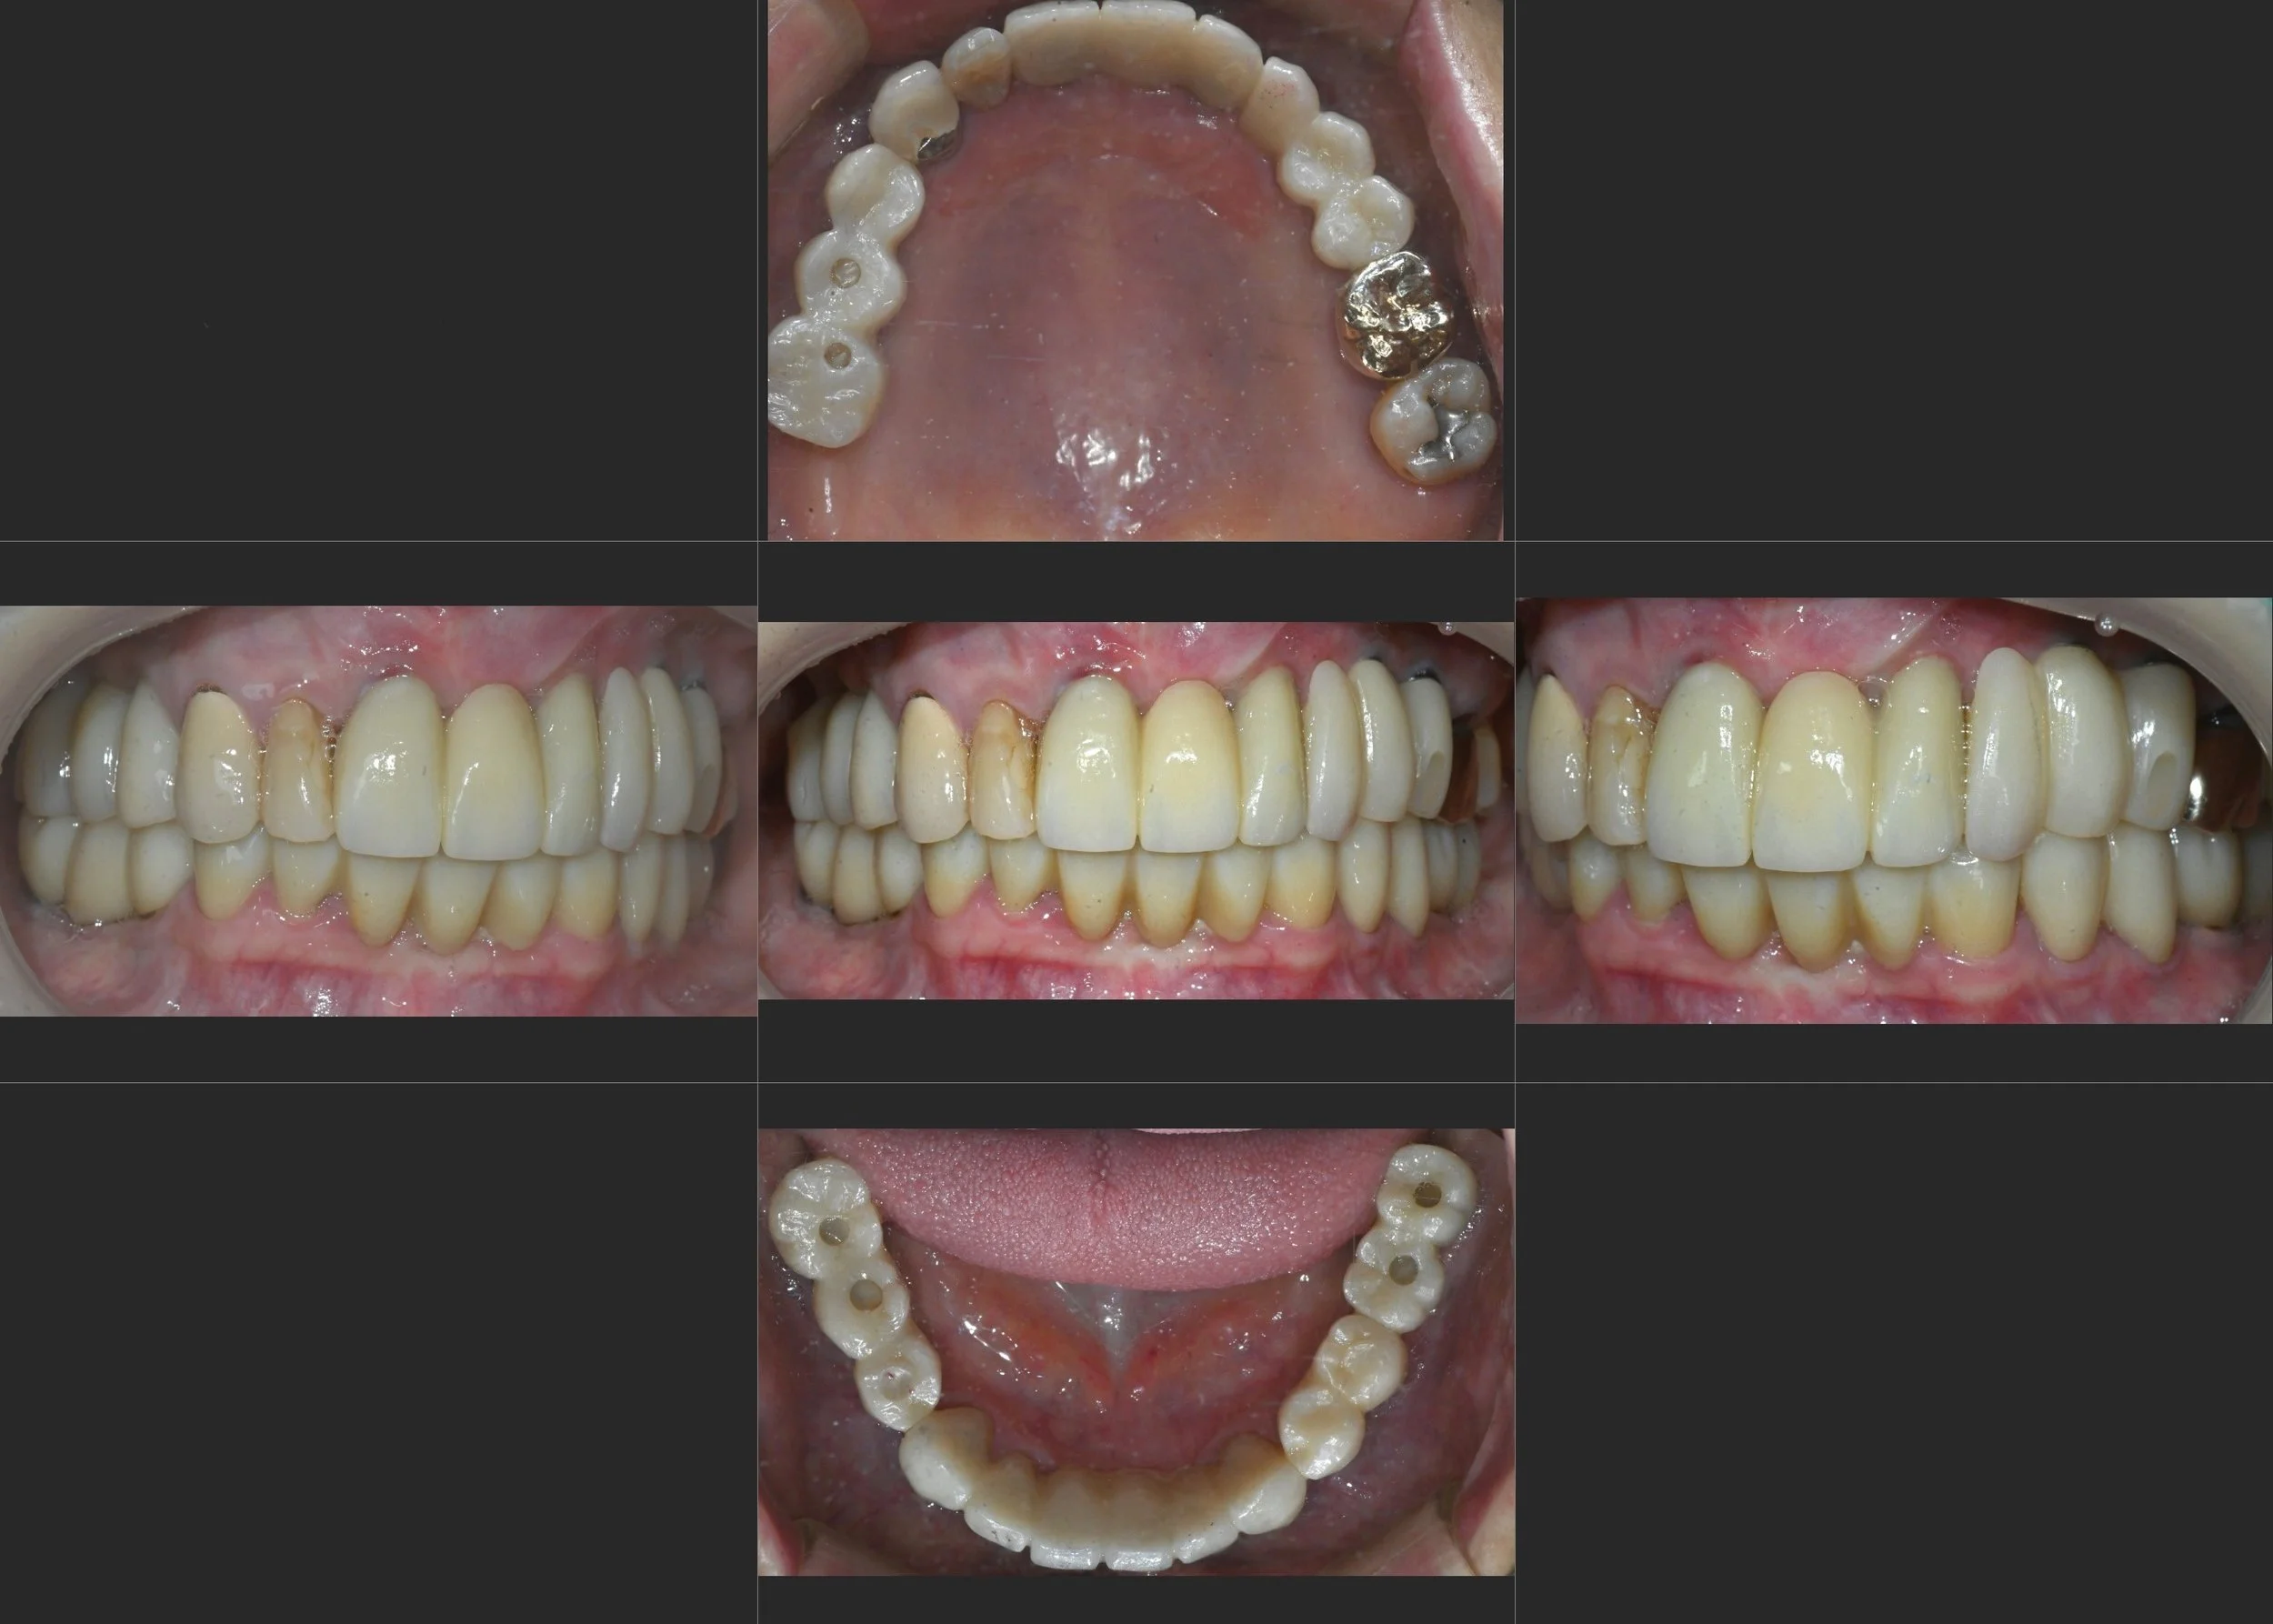

OPG - BEFORE

INTRA ORAL - BEFORE

A female patient in her 50s presented with a severely compromised dentition and significant functional distress. Having relied on ill-fitting partial dentures for a long period, the lack of stable posterior support had led to:

• Occlusal Collapse: Loss of posterior bite force and a resulting decrease in Vertical Dimension of Occlusion (VDO).

• Advanced Periodontal Disease: Severe horizontal and vertical bone loss across both arches, with significant tooth mobility.

• Prosthetic Failure: The existing removable and fixed prosthetics were no longer functional, exacerbating alveolar bone resorption.